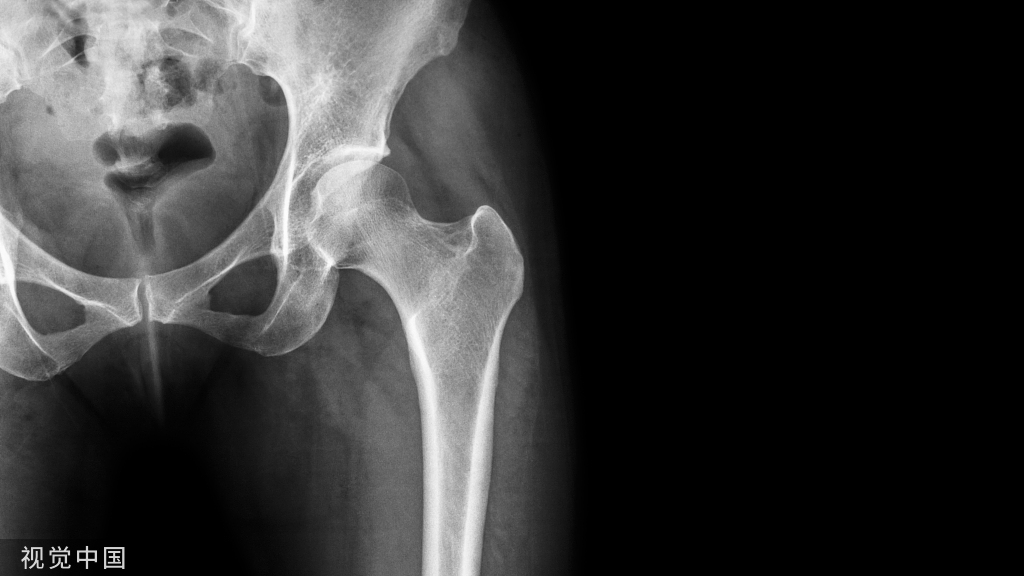

2019年,73岁的张老先生因腿部疼痛,开始无法正常行走,后通过在爱康体检筛查出膝关节和髋关节都出现了问题。

但出于对髋关节置换手术的害怕、恐惧,髋关节的问题张老先生一直不敢面对,可他也深知如果一拖再拖,将来发展严重会对行动产生不可逆的影响……从抗拒手术到2022年术后2天就可以下床走动,张老先生通过人工智能精准评估骨骼状况并找到了最佳的手术方案。

“50岁以上体检人群中,骨量减少以及骨质疏松的检出率超过50%⁵,国人的骨健康现状令人堪忧。骨关节疾病的筛查并非体检中心的常规体检项目,但有了长木谷®的骨科人工智能的赋能,这一原本需要骨科专科医生才能做的检查项目,现在通过X线拍摄下肢关节、然后通过人工智能技术就能完成评估,之后对于需要进行关节置换的患者,通过骨关节CT影像进行三维重建,就能精准匹配人工关节并提供手术方案,这一切如今在体检中心就能完成,之后为患者3D打印手术导板,对接到骨科专科医院进行手术。手术康复一段时间之后,对于人工关节拍片,通过三维重建,就能评估手术后的康复状况,这一服务体系的建立,对于骨健康的管理可以说是一个革命性的变化”,作为国内预防医学领域的先行者,爱康集团创始人、董事长兼CEO张黎刚进行《AI“破局”骨关节健康管理》的主题演讲时强调骨关节疾病早筛的重要性,“体检中心作为社会广泛人群健康筛查的第一道关卡,将创新科技应用在健康全管理过程中,是能够帮助体检人群实现更早发现、更早诊断、更早治疗”。